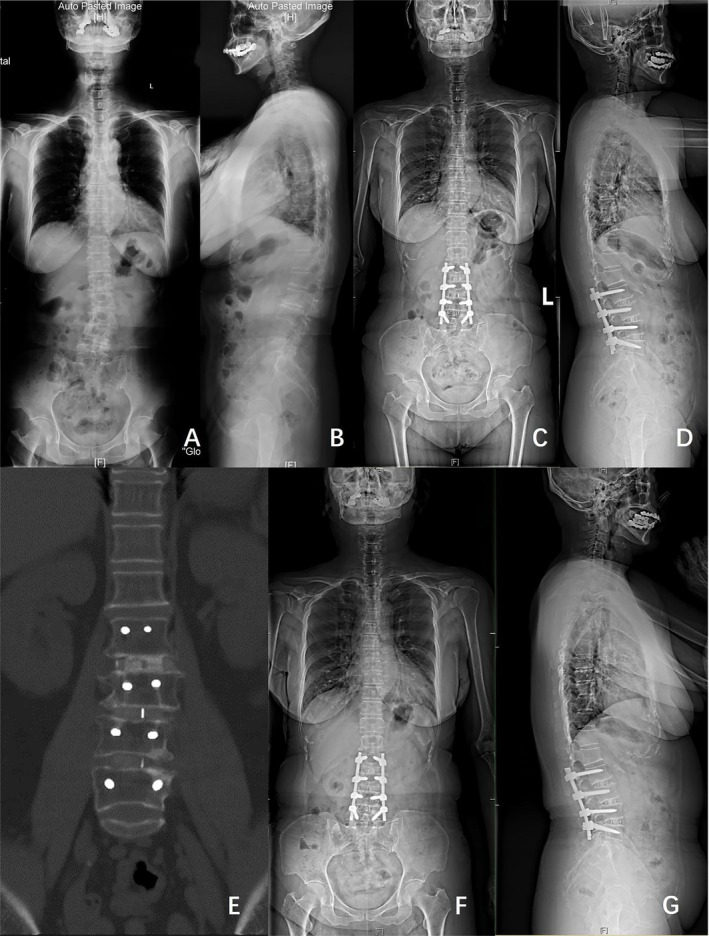

Figures 2 and 3 show classical examples of OLIF and posterior‐only approach surgery, respectively.